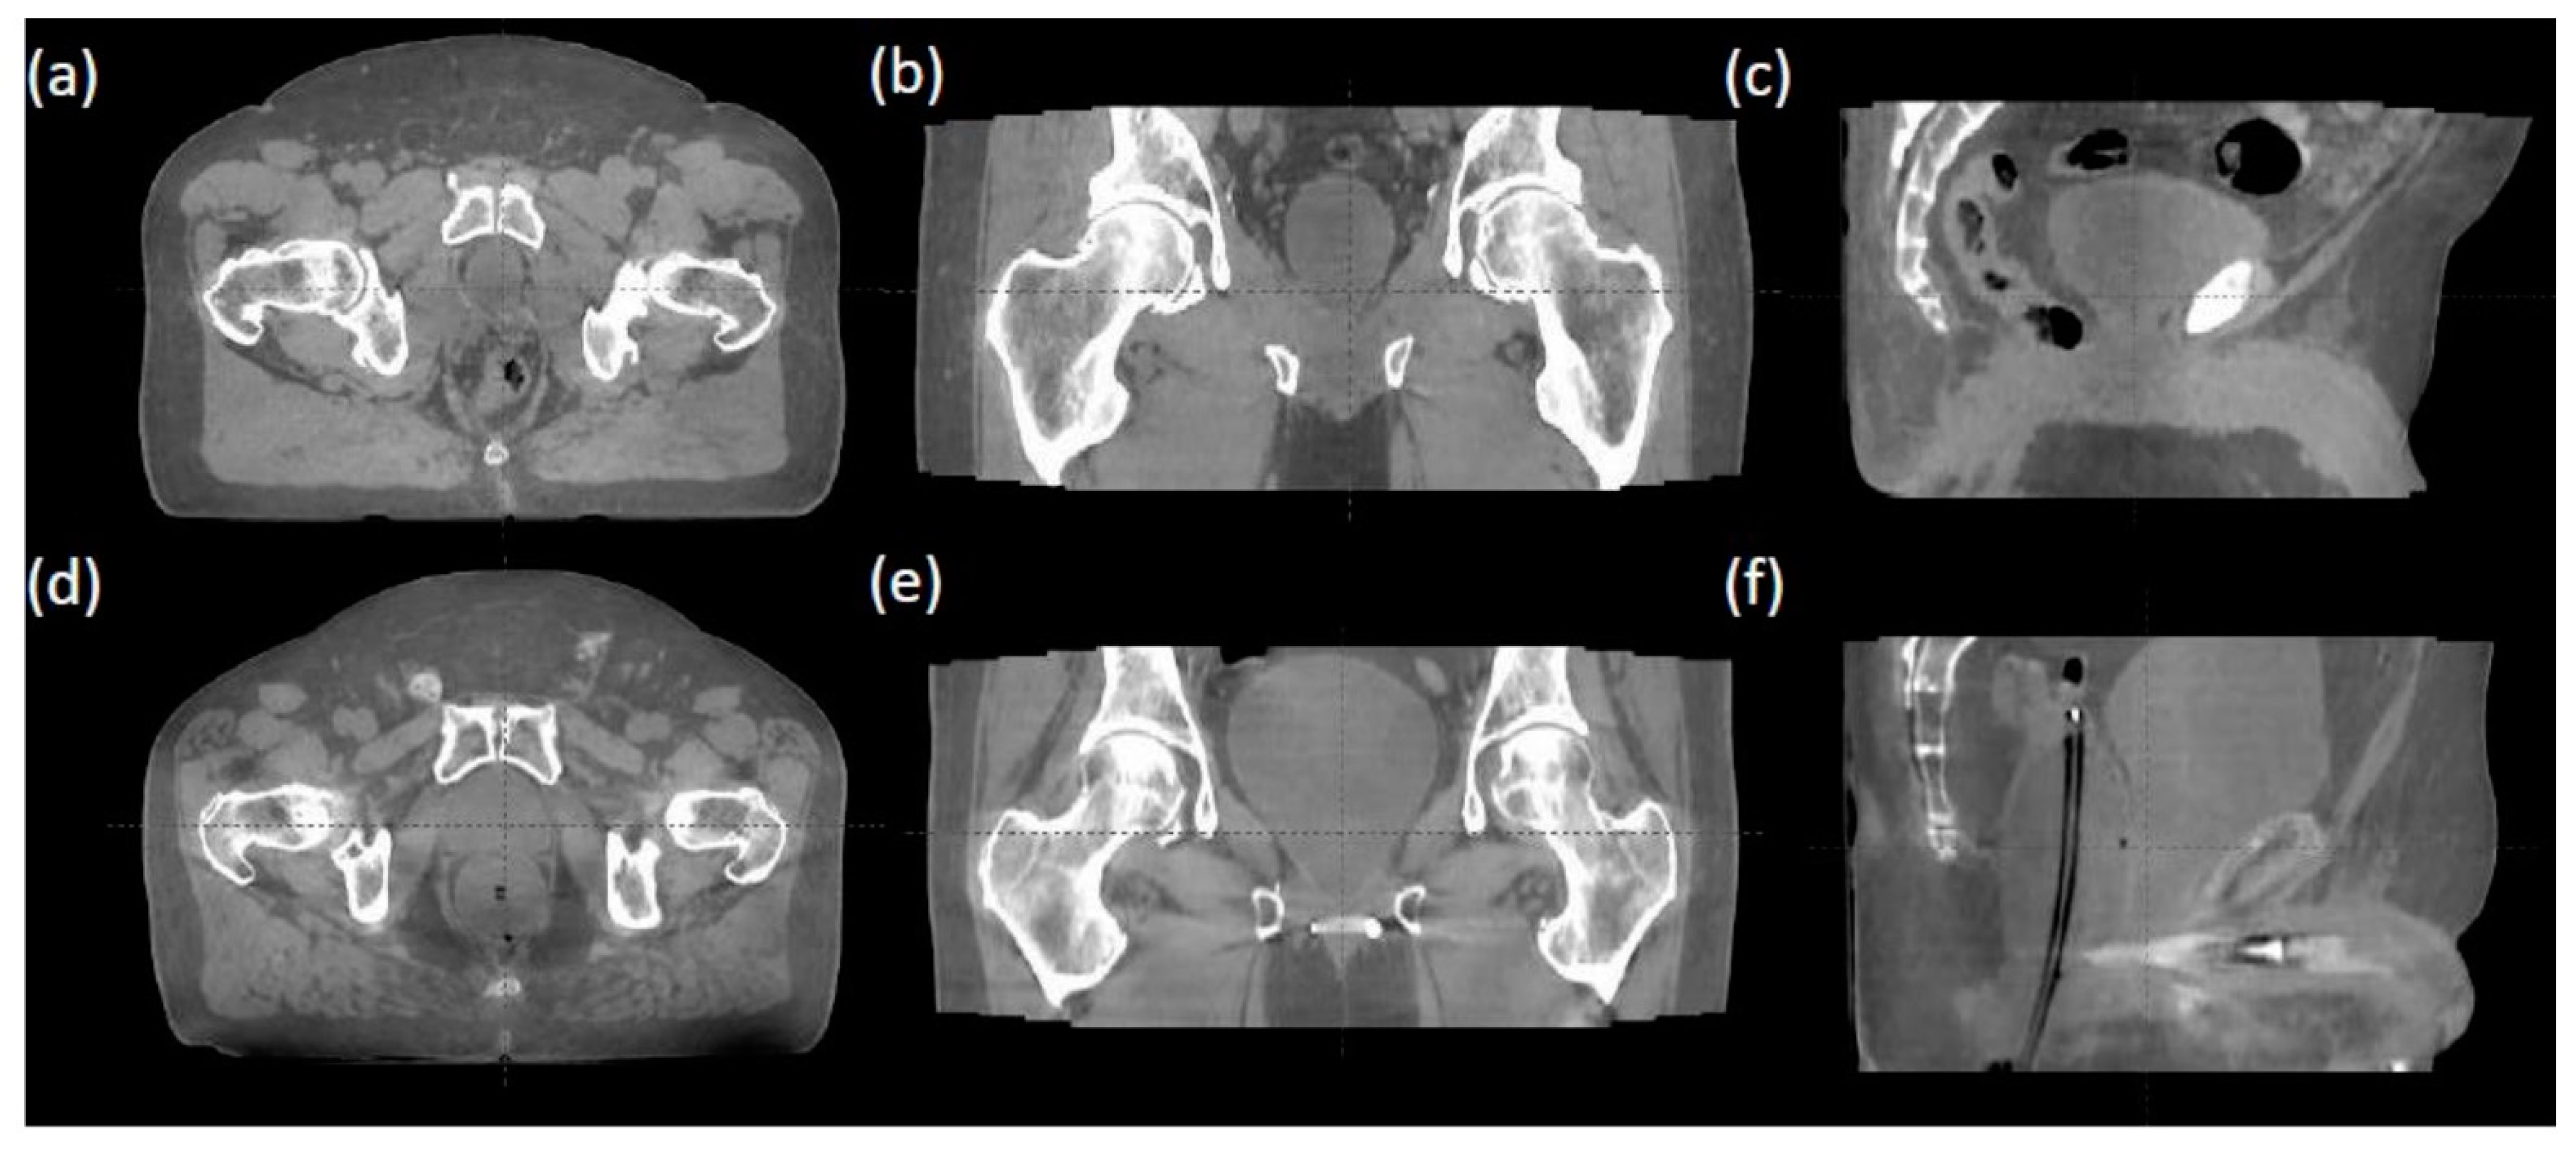

- Jarema, T.; Aland, T. Using the iterative kV CBCT reconstruction on the Varian Halcyon linear accelerator for radiation therapy planning for pelvis patients. Phys. Medica 2019, 68, 112–116. [Google Scholar] [CrossRef] [PubMed]